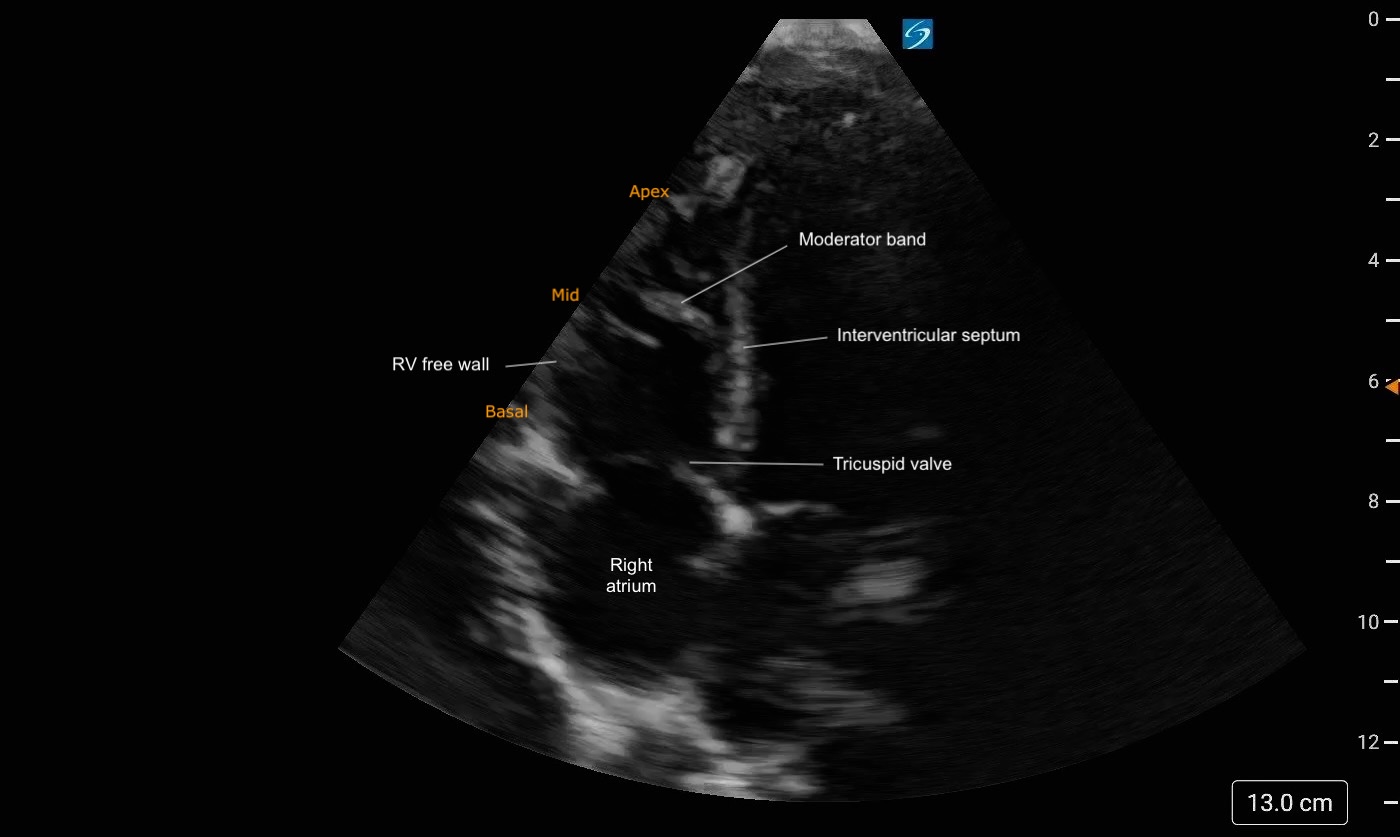

Apical Four Chamber

In A4C view, you can assess LV wall motion at the basal, mid, and apical levels of the inferoseptal and anterolateral walls (figure 19). This view is also useful for visual estimation of overall contractility and evaluation of the LV’s size and shape throughout systole and diastole.

It is important to avoid foreshortening in the A4C view, as this can underestimate LV length and overestimate function. If the LV appears round or blunt at the apex, the image is likely foreshortened—slide the probe laterally and slightly inferiorly to better align with the cardiac apex, and angle it more anteriorly (toward the face) to bring the true apex into view and ensure a full-length chamber.

Figure 19: Apical 4 Chamber view in cardiology convention with the labeled left ventricular walls

The apex and visible LV walls (inferoseptal and anterolateral) should move inward toward the center, with the base also moving toward the apex. All walls should demonstrate coordinated inward motion and uniform thickening.

Eyeballing Ejection Fraction:

When qualitatively assessing LV function in the A4C view, the EF can often be ‘eyeballed’. The LV cavity should visibly reduce its volume by more than half with each contraction. Longitudinal shortening will also contribute to overall cavity reduction.